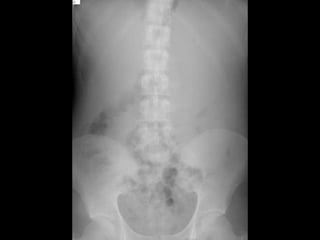

La rotura espontánea del bazo es una causa rara pero potencialmente letal de dolor abdominal que puede deberse a alteraciones congénitas, infecciones, enfermedades metabólicas, neoplasias, inflamación o alteraciones vasculares. Los síntomas incluyen dolor abdominal que se generaliza, distensión abdominal y signos de irritación peritoneal. El diagnóstico se realiza mediante cuadro clínico, exámenes de laboratorio, placa de abdomen, ecografía, lavado peritoneal o TC, y el tratamiento implica líquidos intra